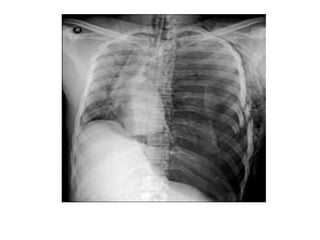

Pneumotórax hipertensivo

MECANISMO DE TRAUMA:

• choque do tórax contra anteparos (volante

de veículo, quedas, entre outros) ou de

objetos contra o tórax (agressões, coices

de animais), atropelamento, explosões,

soterramento, desacelerações súbitas,

ventilação mecânica.

Quando suspeitar? na presença de:

•

• Extrema ansiedade, taquipnéia intensa, taquicardia,

hipotensão, cianose, dor torácica, respiração superficial;

Sinais precoces: ruídos respiratórios ausentes ou

diminuídos do lado afetado, aumento progressivo da

dispnéia e taquipnéia, apesar do tratamento, percussão

timpânica;

Sinais tardios: ingurgitamento da veia jugular, desvio da

traquéia, sinais de hipóxia aguda, timpanismo à

percussão do tórax, pressão de pulso diminuída,

hipotensão, sinais de choque descompensado.